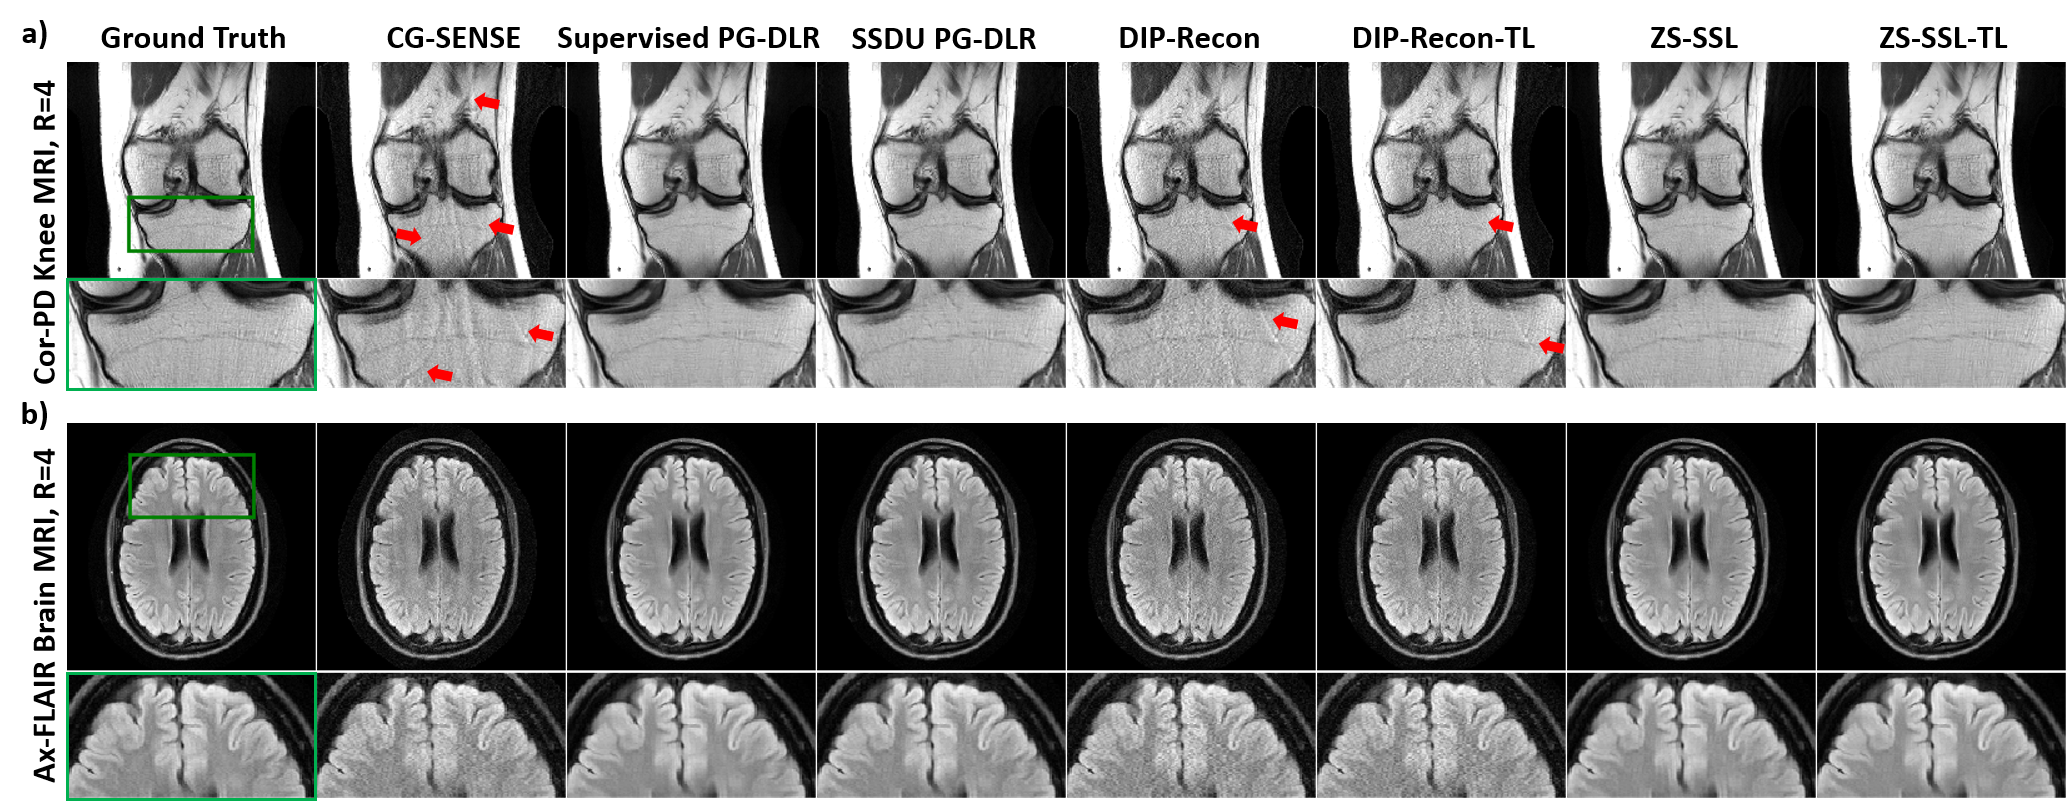

Figure 3: Reconstruction results on a representative test slice from a) Cor-PD knee MRI and b) Ax-FLAIR brain MRI at R = 4 with uniform undersampling. CG-SENSE, DIP-Recon, DIP-Recon-TL suffer from noise amplification and residual artifacts shown with red arrows, especially in knee MRI due to the unfavorable coil geometry. Subject-specific ZS-SSL and ZS-SSL-TL achieve artifact-free and improved reconstruction quality, similar to the database-trained SSDU and supervised PG-DLR.

Comparison of Reconstruction Methods: In these experiments, supervised and SSDU PG-DLR are trained and tested using uniform undersampling at R = 4, representing a perfect match for training and testing conditions. Figure 3a and b show reconstruction results for Cor-PD knee and Ax-FLAIR brain MRI datasets in this setting. CG-SENSE reconstruction suffers from significant residual artifacts and noise amplification in Cor-PD knee and Ax-FLAIR brain MRIs, respectively. Similarly, both DIP-Recon and DIP-Recon-TL suffer from residual artifacts and noise amplification. Supervised PG-DLR achieves artifact-free reconstruction. Both ZS-SSL and ZS-SSL-TL also perform artifact-free reconstruction with similar image quality. Table 1 shows the average SSIM and PSNR values on 30 test slices. Similar observations apply when random undersampling is employed (Figure 10 in the Appendix). For the remaining experiments, we investigate the generalizability of database-pretrained models using supervised PG-DLR as baseline due to its higher performance, while noting SSDU PG-DLR, which is a self-supervised database-trained model, may also be used as a baseline if needed.